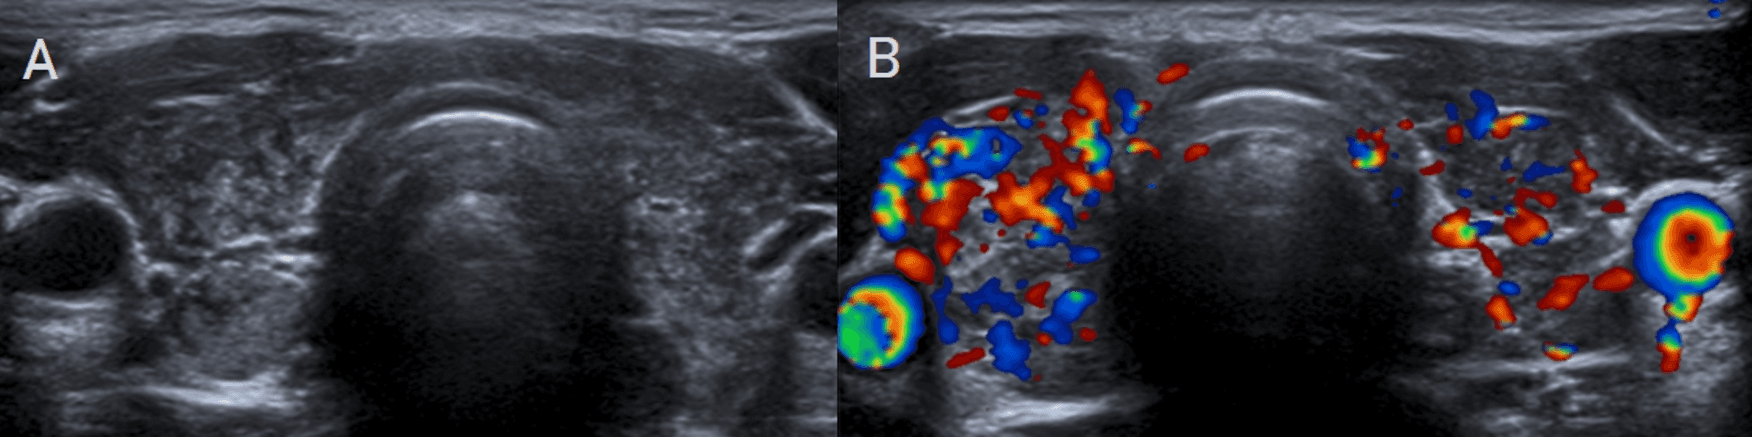

Cuando la clínica es ambigua, la ecografía con Doppler se convierte en la herramienta decisiva para distinguir las dos grandes entidades autoinmunes. En la tiroiditis de Hashimoto, el patrón clásico combina aumento difuso de la glándula, múltiples micronódulos hipoecogénicos rodeados por septos finos hiperecogénicos, conocido como patrón en jirafa, además de nódulos sólidos hiperecogénicos tipo white-knight. Aunque puede existir hipervascularización, las velocidades picosistólicas suelen mantenerse en rangos no francamente elevados. En la enfermedad de Graves-Basedow, en cambio, la firma diagnóstica es el infierno tiroideo: hipervascularización difusa y marcada, acompañada de velocidades picosistólicas claramente elevadas, en general por encima de 60 a 70 cm/s. La diferencia no es solo estética. Es hemodinámica, funcional y terapéutica.

La tiroiditis de Hashimoto desplaza la interpretación tiroidea desde la lesión focal hacia el reconocimiento de un patrón difuso con firma propia. En Doppler color, la combinación de ecoestructura heterogénea, micronódulos hipoecogénicos rodeados por bandas lineales hiperecogénicas y vascularización no marcadamente aumentada construye un fenotipo ecográfico de alto valor diagnóstico. Para el radiólogo, esta imagen resume una enseñanza clave: no toda glándula heterogénea hipervascular corresponde a Graves; en Hashimoto, la arquitectura parenquimatosa sigue siendo el dato rector y el Doppler actúa como herramienta de precisión para evitar sobreinterpretaciones hemodinámicas.

Uno de los errores más frecuentes en imagen tiroidea es asumir que el aumento difuso de tamaño y la hipervascularidad visual bastan para concluir Graves. No siempre es así. Hashimoto puede simular actividad vascular aumentada, y solo la cuantificación Doppler permite separar un patrón linfocítico crónico de una tirotoxicosis franca. En este punto, la medición supera a la impresión cualitativa. El valor del Doppler espectral no está solo en confirmar flujo: está en objetivar comportamiento biológico.